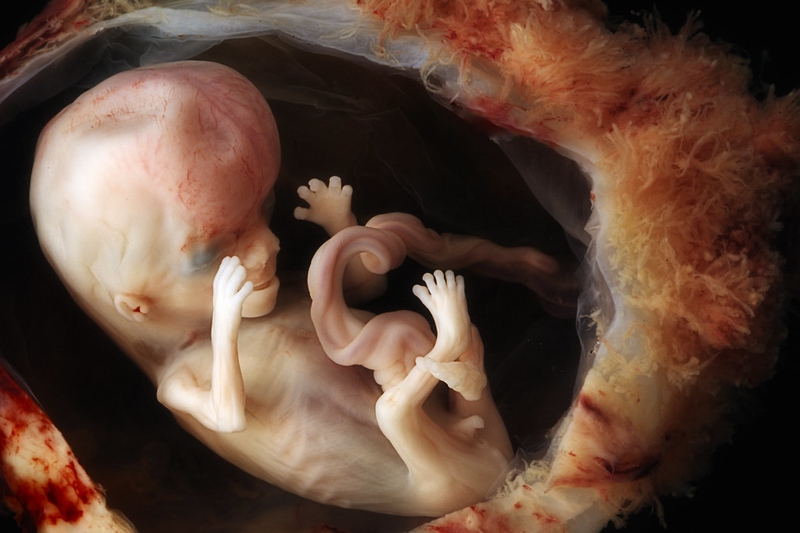

Sự phát triển của thai nhi 12 tuần tuổi

Sau đây là những sự thay đổi lớn của thai nhi ở 12 tuần tuổi:

• Phát triển khả năng phản xạ: Thai nhi ở thời điểm này có thể co duỗi các ngón chân, nhắm chặt mắt và phản ứng lại nếu như gõ nhẹ vào bụng mẹ.

• Tim thai đập nhanh và mạnh hơn: Tim thai lúc này đã nghe rõ ràng hơn và thường đập nhanh hơn từ 2 đến 3 lần so với nhịp tim của mẹ.

• Phát triển xương và các chi: Xương khớp của thai nhi dần cứng cáp hơn, các ngón chân, ngón tay tách rời và xuất hiện dấu vân tay.

• Gương mặt dần hoàn chỉnh: Hai mắt của trẻ gần lại và di chuyển về phía trước, trong khi đó tai di chuyển về phía sau.

• Ruột và thận tương đối hoàn chỉnh: Thức ăn đã có thể di chuyển vào dây rốn vào ruột và thận bắt đầu bài tiết nước tiểu.

• Cơ quan sinh dục trong quá trình hoàn thiện: Thai nhi dần xuất hiện bộ phận sinh dục trong giai đoạn này.

Giải đáp thắc mắc: Siêu âm 12 tuần đã biết trai hay gái chưa 1 Thai nhi 12 tuần tuổi đã dần hoàn thiện cơ quan sinh dục